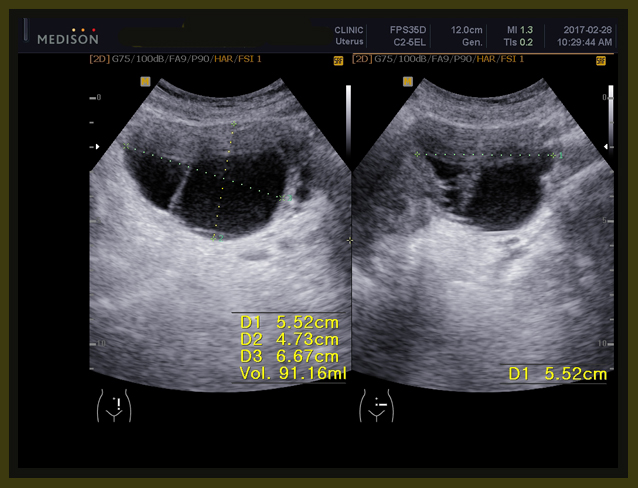

환자는 1년 전에 난소의 양성종양으로 수술을 받았던 경험이 있고, 이번에도 유방수술 이후에 초음파를 보니 83mm x 61 mm x 58 mm의 약 8cm x6cm 정도의 격벽으로 분리된 cystic mass 즉 액상의 종양이 보였고, 또한 13mm, 15 mm의  mass도 발견되었다(2017년 1월 26일 검사).

내원 후에 본원 의뢰하여서 초음파 검사를 하였는데 초음파상의 결과는 이전 병원과 약간의 차이가 있지만 역시 8cm가 넘는 종양이 발견되었다.

골반초음파

1. 6.8cm x 5.9cm x 8.1 cm 크기의 여러 개로 갈라진 격벽을 가지고 있는 액상의 부위가 왼쪽 자궁주위 조직에 보이는데 양성의 혹으로 보인다.

2. 자궁내막의 비후가 관찰된다.

3. 약 3cm 크기의 근종으로 의심되는 부분이 자궁의 아래쪽에 보인다.

1. 6.8cm x 5.9cm x 8.1 cm 크기의 여러 개로 갈라진 격벽을 가지고 있는 액상의 부위가 왼쪽 자궁주위 조직에 보이는데 양성의 혹으로 보인다 (volume 171 CC).

2주간의 한양방 결합요법의 결과 3항에서 보듯이 약 7mm 정도의 전에 잔류 종양으로 보이던 부분이 약간 줄어들었고, 자궁주위에 있던 난소의 종양은 6.8×5.9x 8.1cm의 크기가 5.5×4.7×6.7cm 로 체적대비해서 171 cc가 91 cc로 100%의 종양이 53%로 절반 가량이 줄어들었고, 자궁내벽의 비후는 여전히 보이고, 3cm 크기의 근종으로 보이는 종양은 차이가 없었다.